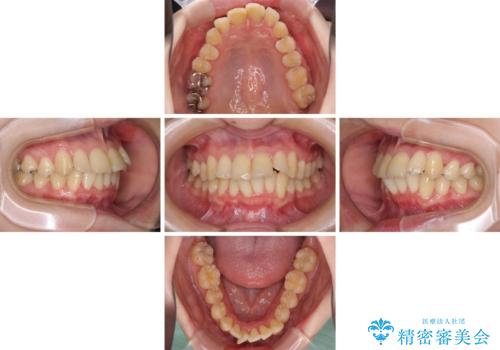

上下前歯のデコボコをきれいに インビザラインによる矯正治療

- 前歯の著しい叢生と前突感を気にして来院された患者様です。

叢生が強いため、事前に前歯をワイヤー矯正で速やかに叢生を解消し、その後はインビザラインにて矯正治療を行うこととしました。

ワイヤー矯正を併用したことで前歯の叢生を速やかに解消することができました。

一方口元の突出感を改善するために時間がかかり、2年超を要しましたが、満足のいく仕上がりとなりました。